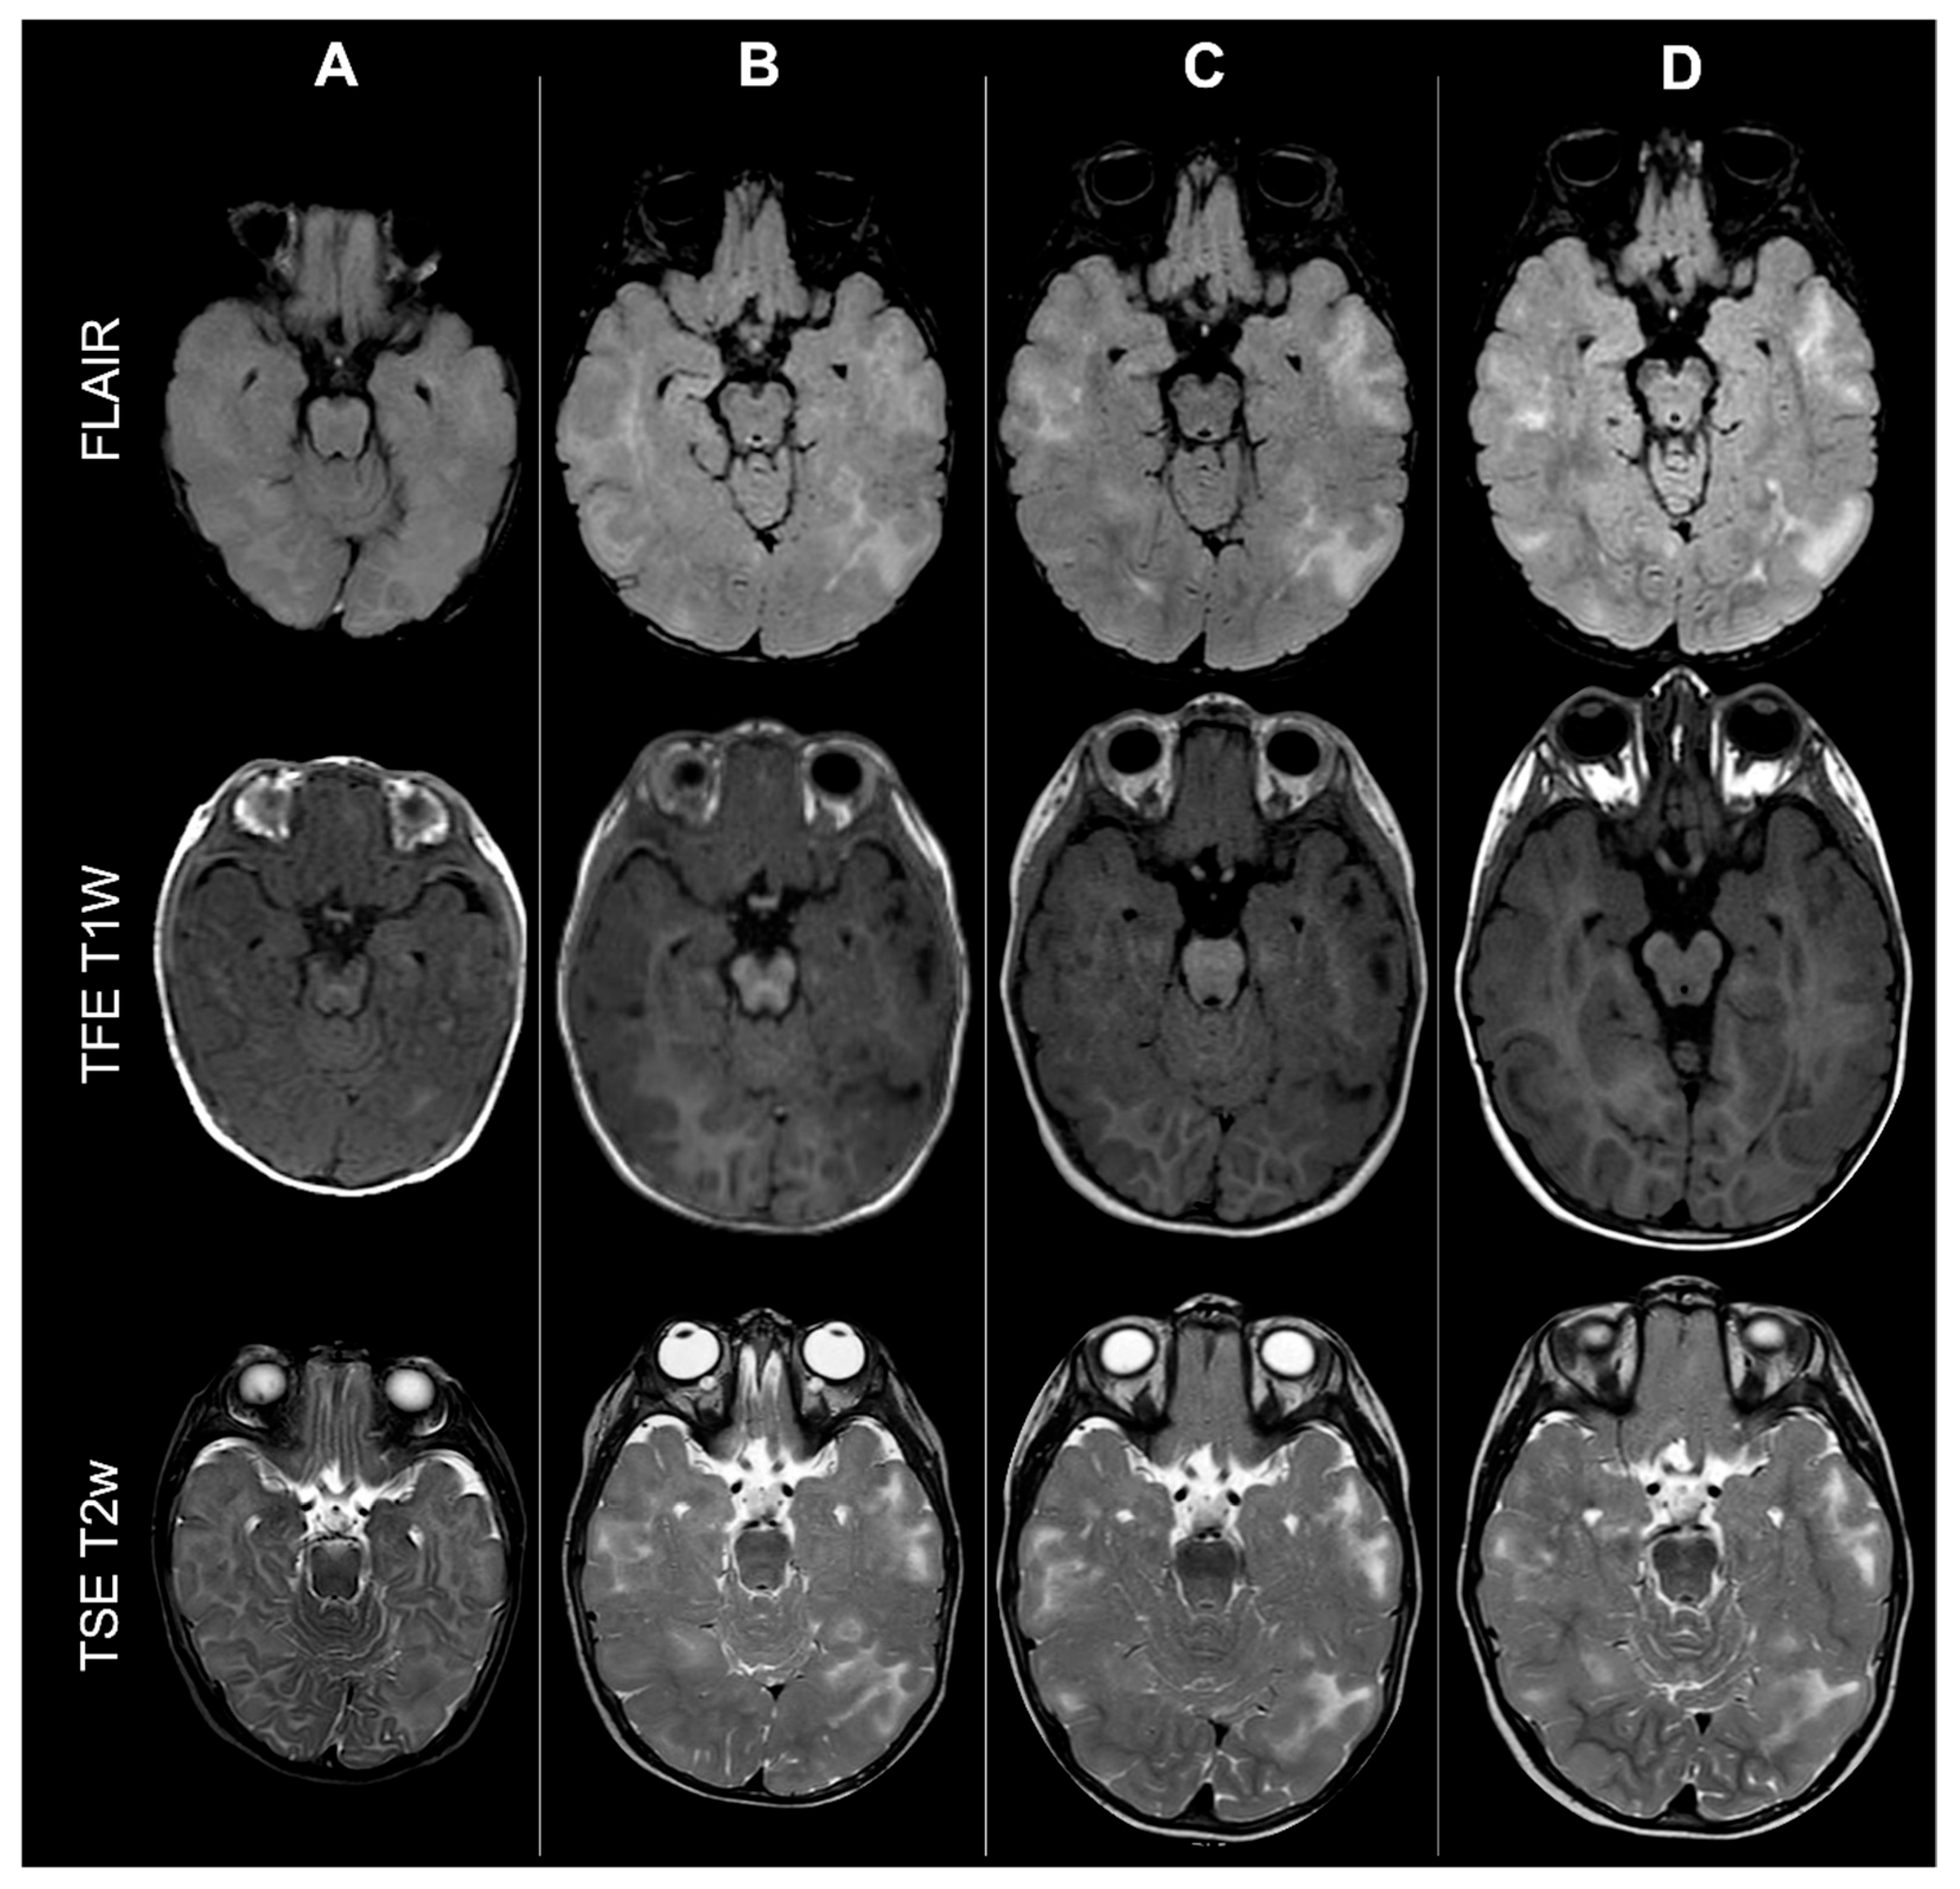

Concerning total lesion count, the interobserver agreement was excellent, with an ICC of 0.91 (95% CI: 0.87–0.95). At baseline, the total number of CTs identified across the cohort was 918 (mean ± SD = 16.1 ± 12.4), whereas at the last available MRI follow-up, the overall count increased to 1070 (mean ± SD = 18.8 ± 13.3), corresponding to a net gain of 152 CTs, equal to a relative variation of +17%. When stratified by tuber type, distinct trajectories were observed over time. Type A CTs, which were relatively abundant at diagnosis (N = 303, mean ± SD = 5.3 ± 7.0), decreased to 255 (mean ± SD = 4.5 ± 5.9) at follow-up, yielding a reduction of 48 lesions (−16%). Conversely, type B CTs showed an opposite trend, increasing from 438 (mean ± SD = 7.7 ± 8.4) at baseline to 556 (mean ± SD = 9.8 ± 8.6) at follow-up, corresponding to a net increase of 118 tubers (+27%). An example of MRI signal evolution from tuber A to tuber B is shown in Figure 1. Similarly, type C1 CTs rose from 160 (mean ± SD = 2.8 ± 4.8) to 220 (mean ± SD = 3.9 ± 5.8), with a net gain of 60 tubers (+38%). Type C2 CTs, initially rare at diagnosis (N = 14, mean ± SD = 0.2 ± 0.8), markedly expanded to 33 (mean ± SD = 0.6 ± 1.5), accounting for an increase of 19 CTs (+136%). Finally, type D CTs were only sporadically encountered, with a modest increase from 3 (mean ± SD = 0.1 ± 0.3) to 6 (mean ± SD = 0.1 ± 0.4), equating to a 100% variation. The observed increment of type C2 tubers was attributable almost exclusively to the progressive transformation of pre-existing type B lesions and, more prominently, type C1 lesions, while the increase in type C1 tubers reflected the gradual conversion of both type A and type B CTs that were already detectable at disease onset. An example of MRI signal evolution from tuber B to C1 is shown in Figure 2, while from tuber C1 to C2 in Figure 3. Only in one patient was a type C1 tuber newly identified at follow-up without clear evidence at baseline. In contrast, newly apparent tubers emerging over time but not clearly visible on baseline scans were most frequently represented by type A and type B lesions. Type D tubers were rare overall and were identified in only six lesions from four patients with a particularly high lesion burden; in all but one case they represented the evolution of type A or type B CTs (an example of MRI signal evolution from tuber A to tuber D is shown in Figure 4), while in a single case they were associated with adjacent subtle calcific foci. Overall descriptive data are summarized in Table 1.

Figure 1.

Left occipital tuber transition from type A to B at three different timepoints in a male patient diagnosed with TSC1.

Figure 5.

Effect of myelination on cerebral cortical tubers’ count: MRI scans from the same male TSC2 patient acquired at four different timepoints (respectively: 6 months old—column A; 18 months old—column B; 36 months old—column C; 4 years old—column D, showing how incomplete myelination in early infancy may impact tubers detection by reducing contrast with surrounding brain tissue.